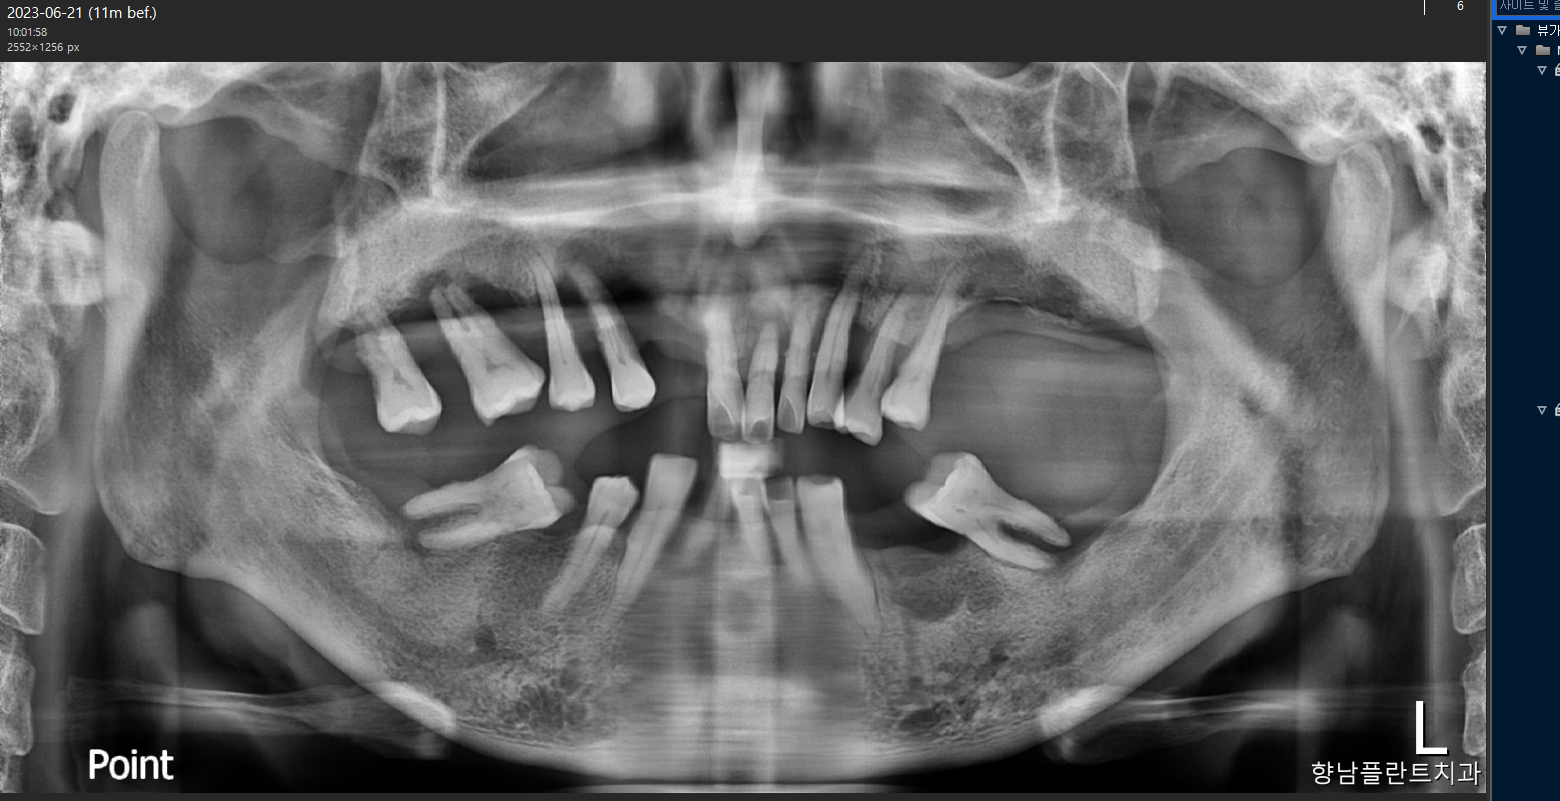

안녕하세요, 365향남플란트치과입니다. ​오늘은 전체임플란트를 받게 되신남성 환자분의 이야기를 드려봅니다.   2023년 6월 21일 (왼쪽 사진) 진료를 시작하셔서약 10개월간의 치료 끝에2024년 5월 21일 (오른쪽 사진) 치료를 마치셨습니다.​남아있는 치아가 많이 없으시고치아 배열이 흐트러진 상황이라전체임플란트로 도와드렸습니다.​치아 색상도 자연스럽게 나왔고무엇보다 임플란트와 뼈의 결합이튼튼하게 이루어졌답니다.​전체임플란트 풀케이스환자분 후기 인터뷰환자분의 실제 후기를인터뷰로 담아보았습니다. *해당 인터뷰와 모든 사진 촬영은 환자의 동의하에 진행되었습니다.​Q. 치료받으면서 어떠셨나요?​A. 처음엔 이렇게 많이 임플란트를심을 거라는 생각은 안 했는데워낙 이가 형편없어서다 하는 게 좋겠더라고요.​처..